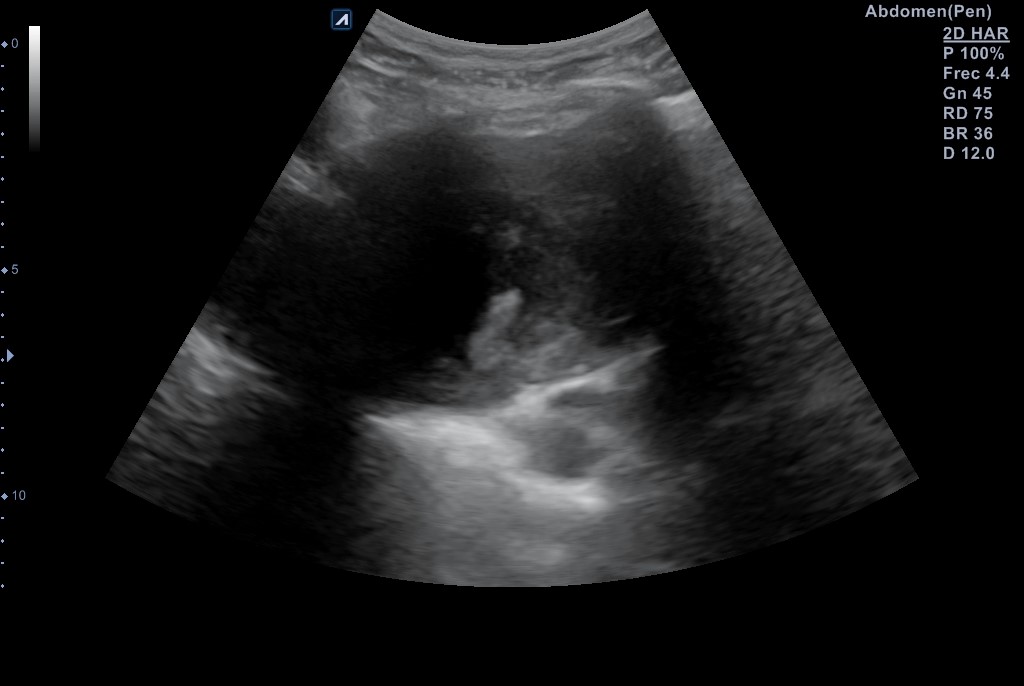

Se realiza ecografía pulmonar donde se identifica una masa anterior en el vértice del pulmón derecho, de aspecto sólido con centro necrótico de unos 7-8 cm de diámetro en anteroposterior y transversal, sin poder precisar diámetro longitudinal por interposición de costillas, clavícula y esternón.